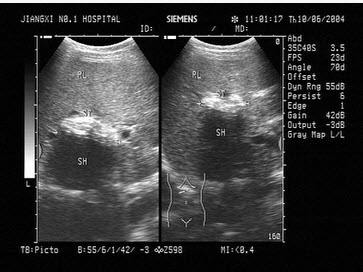

2、黄疸伴肝大